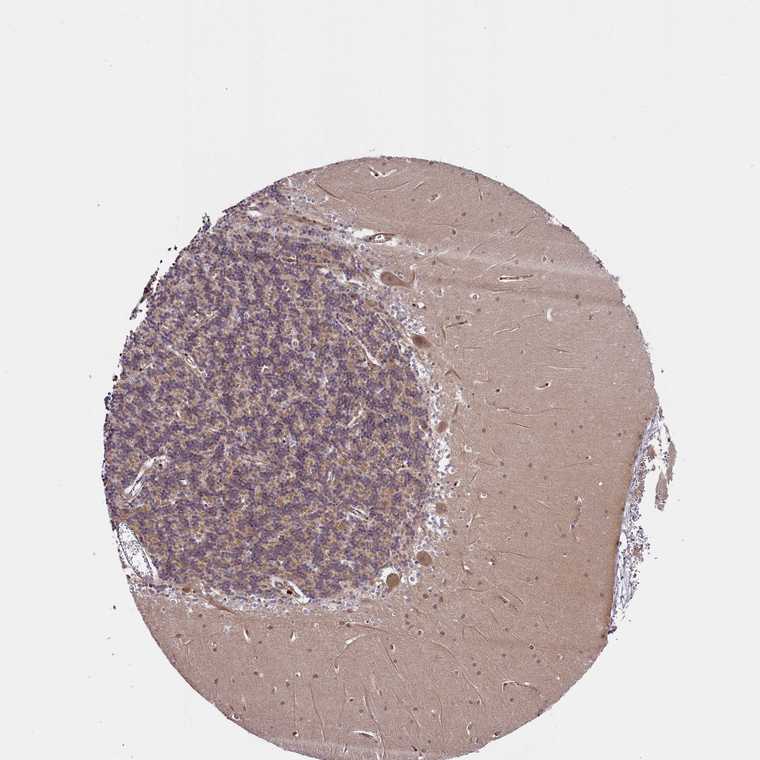

CEREBELLUM - Antibody stainingi

Antibody staining in the annotated cell types in the current human tissue is reported as not detected, low, medium, or high, based on conventional immunohistochemistry profiling in selected tissues. This score is based on the combination of the staining intensity and fraction of stained cells.

Each image is clickable and will lead to virtual microscopy that enables deeper exploration of all samples and also displays staining intensity scores, fraction scores and subcellular localization as well as patient and tissue information for each sample.

Antibody HPA042163

Purkinje cells Medium

Cells in granular layer Medium

Cells in molecular layer Low